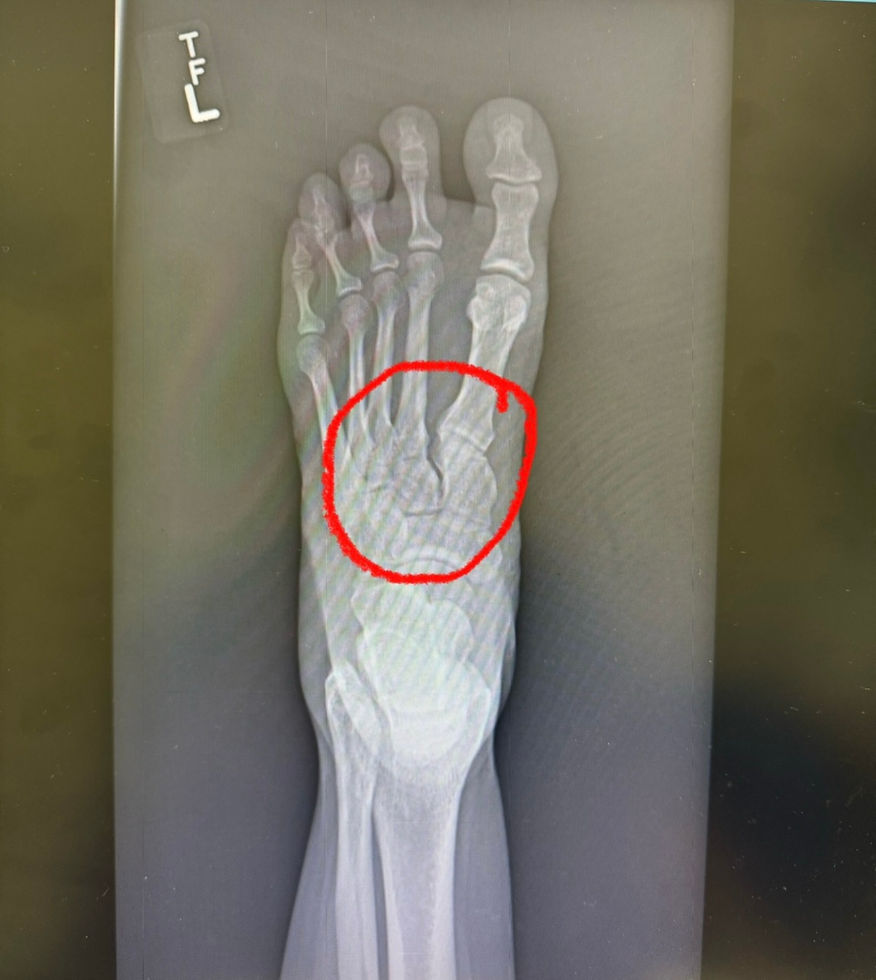

Thanks to some incredible friends- I got into see a specialist the Monday after my injury. Mechanism of injury with the xray - a gap in the xray- was indicative of Lisfranc injury. āNo!!!ā I told the doc. He said āletās think positively, but prepare for the worstā. I knew that was him giving me a little bit of hope but knowing- it was most likely going to require surgery.

Wednesday night, I got the MRI. Friday morning I was at the orthoās office. Confirmed. Lisfranc injury- surgery needed. āItās a serious injuryā, the doc said. Sigh. Ok - letās get it done. I didnāt want to wait and dread it anymore. I just wanted to get it done and move forward.